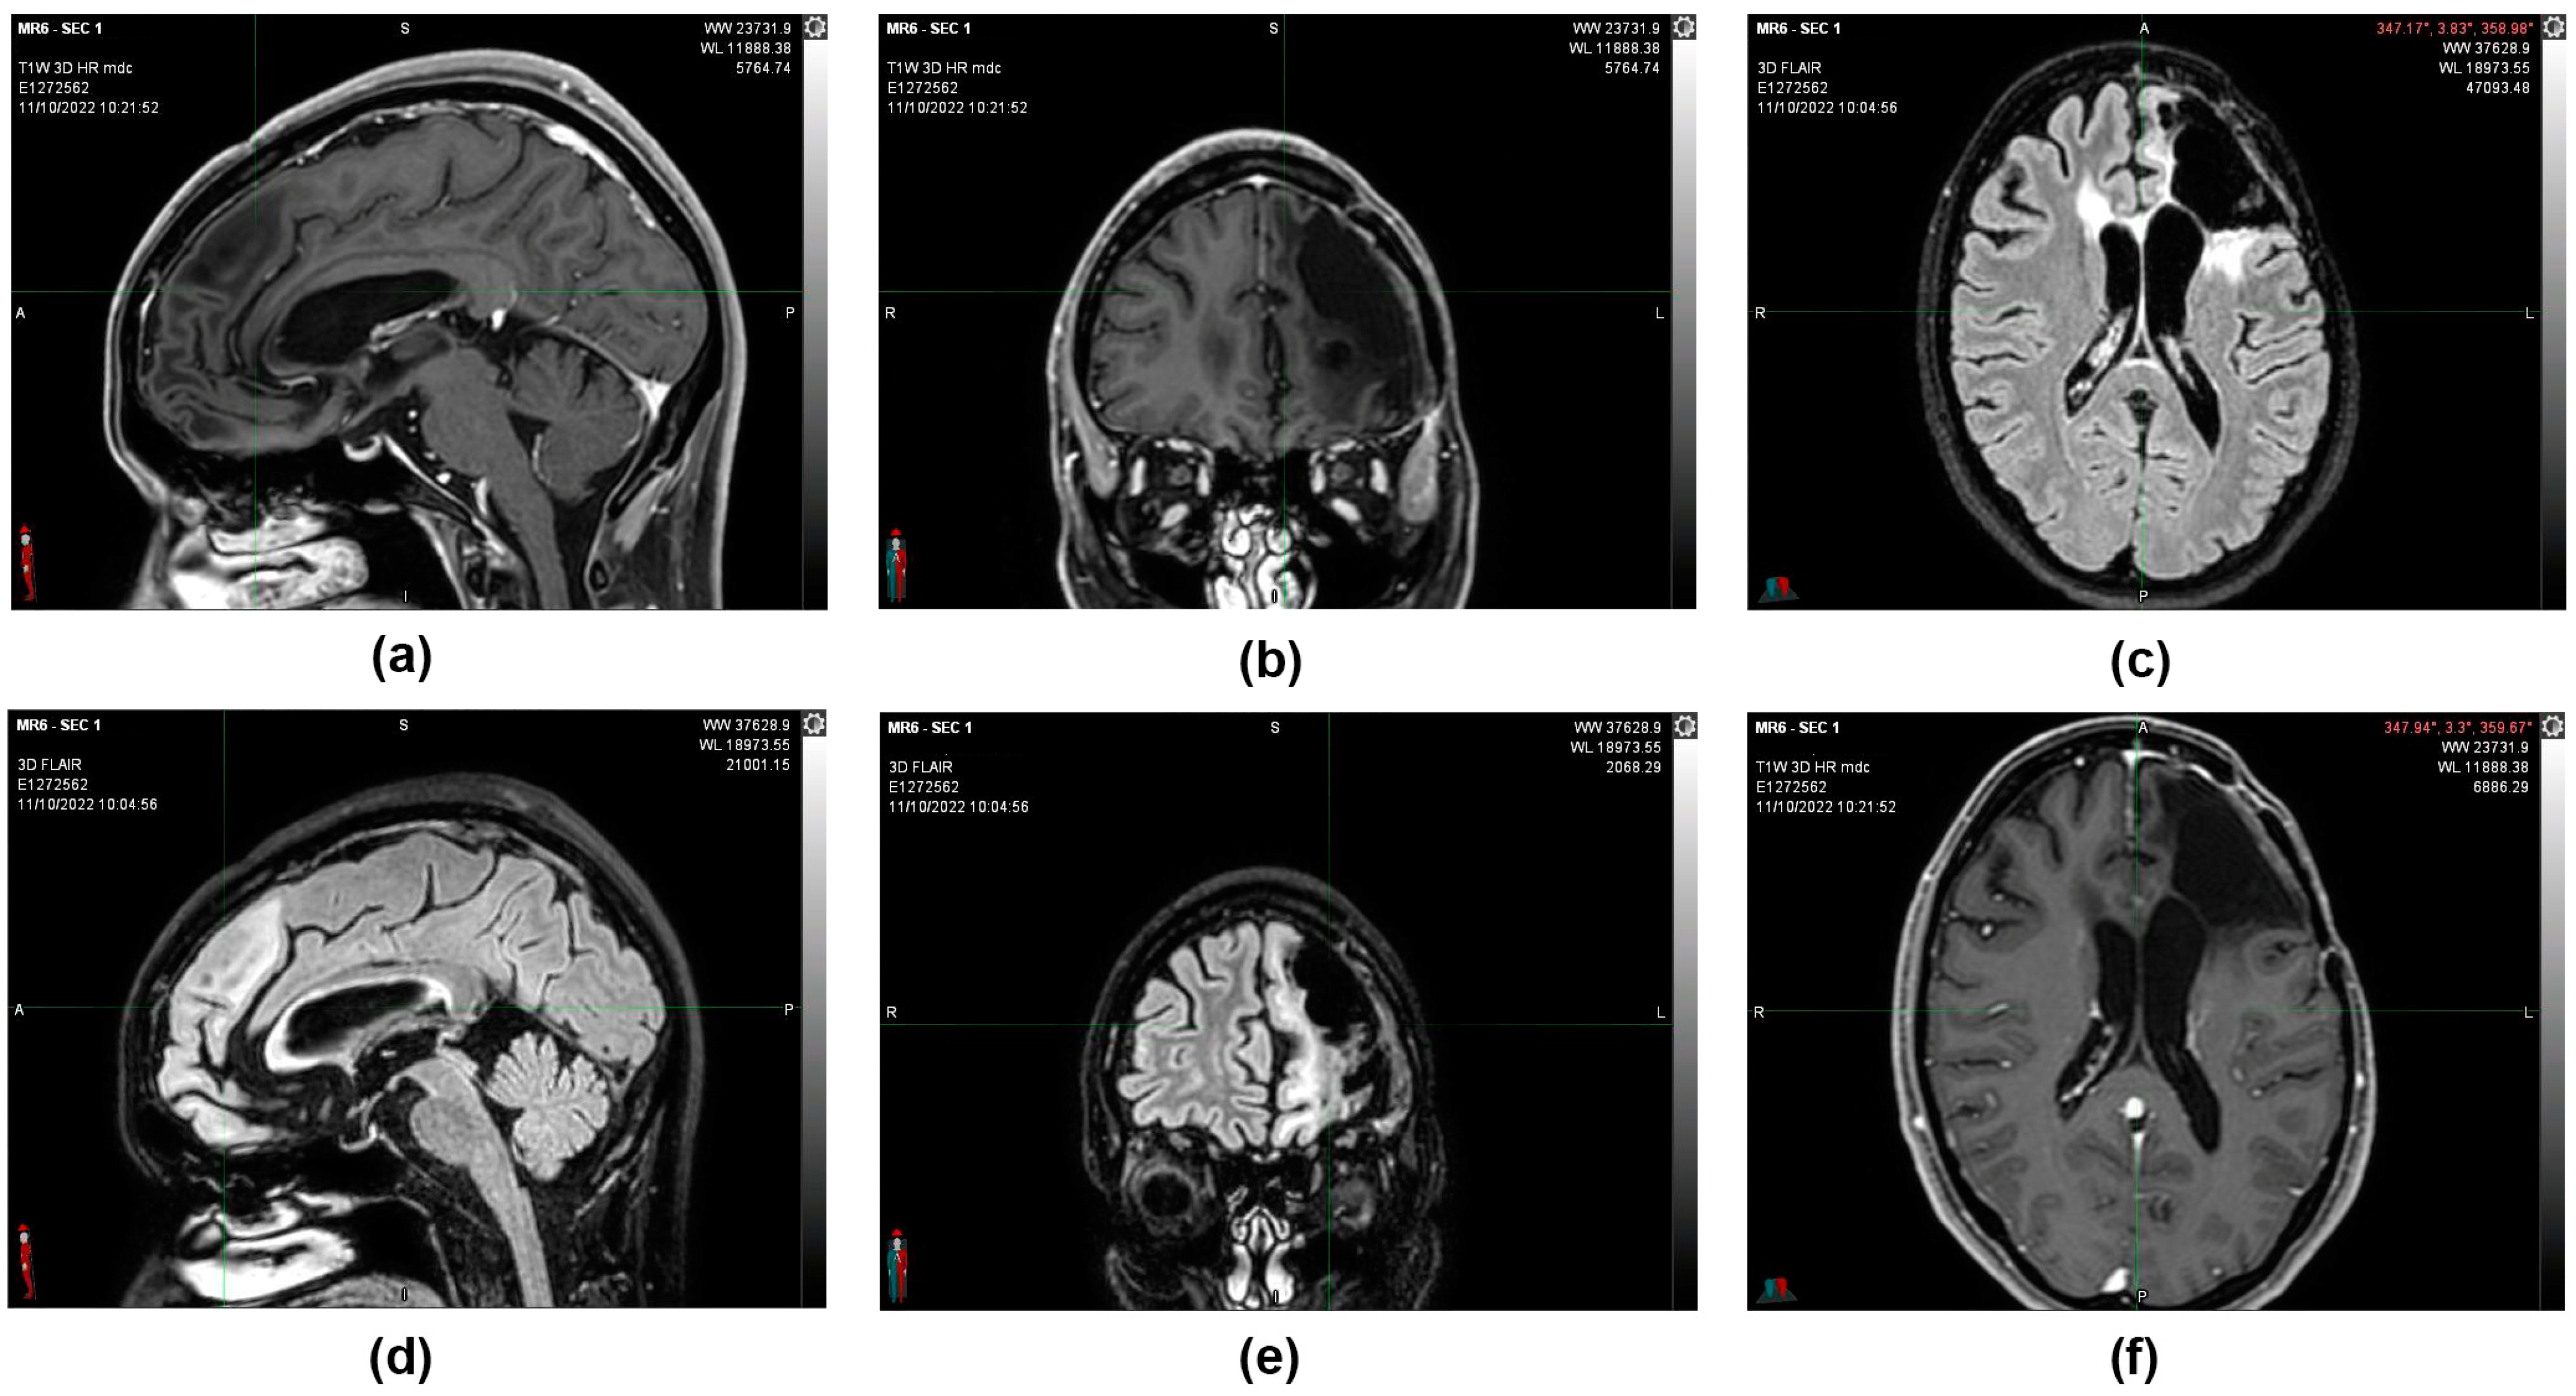

Figure 4.

11 October 2022, instrumental examination, stable negative picture. (a,b,f) MRI images, T1 sequence with contrast medium. (c–e) MRI images, sequence in FLAIR. The morphological picture remained stationary—the T2 hyperintensity surrounding the known left frontal malacic cavity extended to the knee and right root of the corpus callosum and in the left semioval center and was without mass effect and not modified in the contrastographic phases. Non-focality of new onset at the remaining levels. In the spongiosa of the left frontal bone in the median region and on the profile of the operculum, there are two areas of altered signal with contrastographic impregnation, both of which are stationary. The median structures are on an axis. The ventricular cavities and subarachnoid spaces are overlapping in size and morphology.

MRIs were done in subsequent periods (12 July 2021 and 11 October 2022), confirming that the morphological picture remained stable and that the patient was considered cured (Figure 5).

Figure 5.

(a) 21 August 2016, CT image with contrast medium before surgery. (b) 12 October 2016, CT image with contrast medium after partial removal of left frontal multicentric neoplasm. (c) 9 February 2017, MRI image, T1 sequence with contrast medium after the first cycle of oxygen-ozone therapy. (d) 12 July 2021, MRI image sequence in FLAIR. (e) 24 February 2022, MRI image sequence in FLAIR. (f) 11 October 2022, MRI image sequence in FLAIR. Following a total of 5 years after the partial resection surgery, the morphological picture remained stable, and the patient was considered cured.